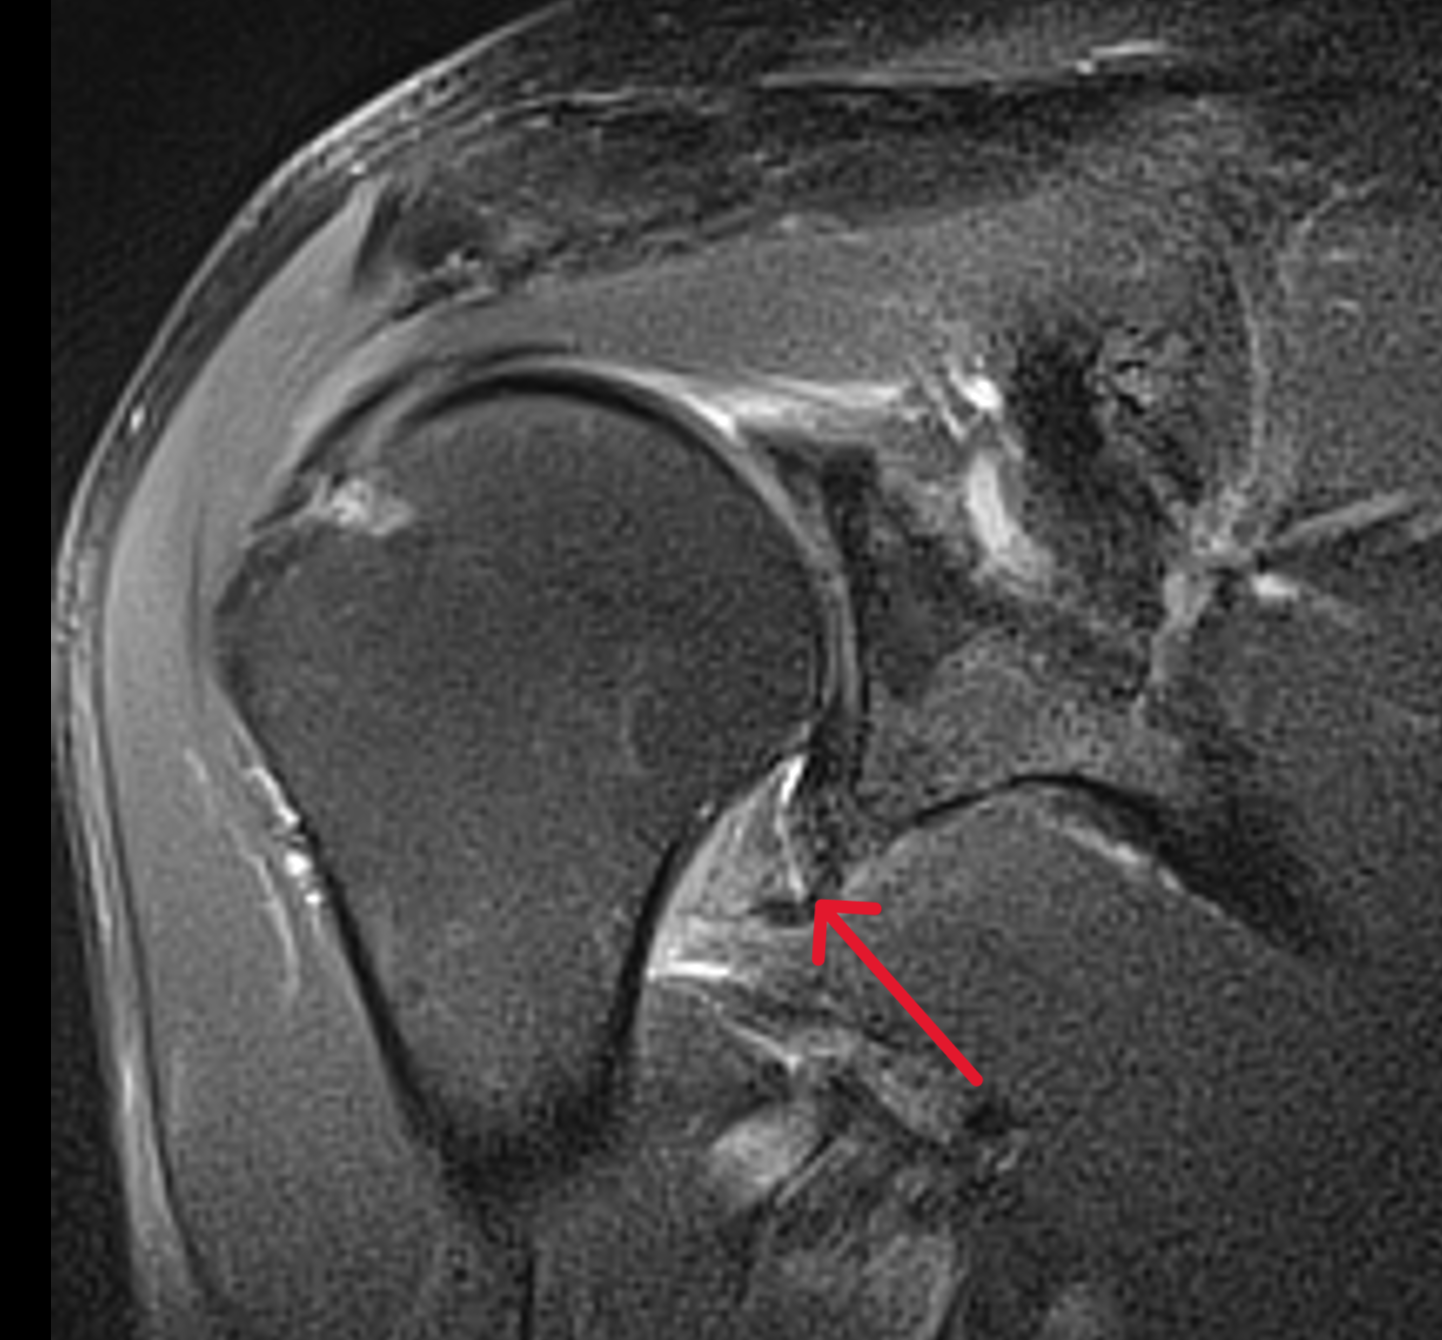

MRI findings of patients with frozen shoulder before and 1 month after X Ray Findings Of Frozen Shoulder However the diagnostic criteria for have remained unchallenged for decades: Web frozen shoulder is still poorly understood on many levels. Web the hallmark sign of frozen shoulder, also known as adhesive capsulitis, is the inability to move your shoulder—either on your own or with the help of. Frozen shoulder can usually be diagnosed from signs and symptoms. Thickening of the. X Ray Findings Of Frozen Shoulder.

mricases Adhesive Capsulitis Frozen Shoulder MRI features X Ray Findings Of Frozen Shoulder Web described direct signs suggestive of frozen shoulder include: Web the hallmark sign of frozen shoulder, also known as adhesive capsulitis, is the inability to move your shoulder—either on your own or with the help of. However the diagnostic criteria for have remained unchallenged for decades: Frozen shoulder can usually be diagnosed from signs and symptoms. Web adhesive capsulitis (also. X Ray Findings Of Frozen Shoulder.

[PDF] MRI Findings for Frozen Shoulder Evaluation Is the Thickness of X Ray Findings Of Frozen Shoulder Web the hallmark sign of frozen shoulder, also known as adhesive capsulitis, is the inability to move your shoulder—either on your own or with the help of. Thickening of the glenohumeral joint. However the diagnostic criteria for have remained unchallenged for decades: Web adhesive capsulitis (also known as frozen shoulder) is a condition of the shoulder characterized by functional loss. X Ray Findings Of Frozen Shoulder.